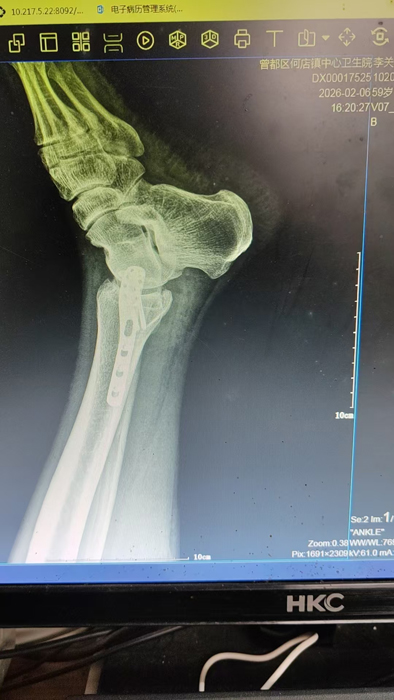

2月4日,何店镇中心卫生院接诊一名左踝关节外伤患者,经影像检查,确诊为左胫、腓骨下段骨折。外科医生姜稳迅速完成术前检查及病情评估,并与患者及家属深入沟通治疗方案。在患者强烈要求于本院进行手术的情况下,为最大限度保障手术质量与安全,该院特邀请医共体牵头单位——曾都区人民医院脊柱创伤外科专家团队前来指导。

本次帮扶由曾都区人民医院脊柱创伤神经外科主任徐三军带队,专家团队抵达后立即完成手术风险评估及术前准备。手术过程中,徐三军主任严格规范完成各项手术操作,并同步结合手术步骤,为该院外科医师详细讲解骨折手术的关键要点、操作技巧、术中注意事项及术后康复要领。通过“手把手”的实战带教,专家将丰富的手术经验与规范的诊疗思路倾囊相授,让该院医护人员在实操中学习,在过程中成长。